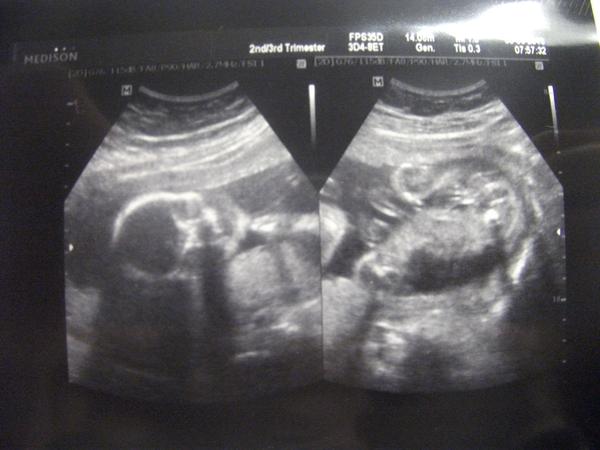

@mariiianka Gratulka k UZ 😵 Krásné fotečky 😉 🙂 Tak to vypadá na klučíka??? Však hlavně, že je miminko zdravé 🙂 🙂 🙂 😉 Já bych naštěstí asi měla jsména pro oba, ale to se jednou uvidí...